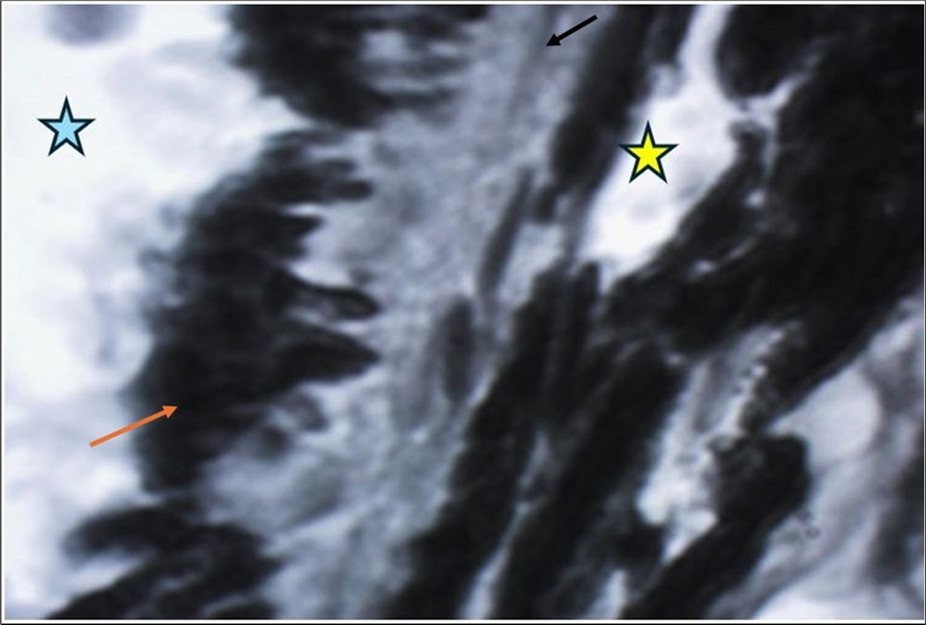

The reported findings of the histologic examinations were identifying photoreceptor and retinal pigment epithelium (RPE) layers to be the major site of injury 6. When the macular region is affected by a closed eye trauma, vision is significantly affected; especially when Bruch's membrane is damaged, because the scarring of this membrane distorts the anatomy of the area (choriocapillaris, pigmented epithelium, photoreceptors) (Figure 1).

Figure 1.Bruch's membrane (black arrow) forms the basement membrane of the cells of the pigmented epithelium of the retina (orange arrow). The yellow star indicates the spaces inside the capillaries in the choroidal layer, and the blue arrow indicates the region that corresponds to the subretinal space, where the retinal photoreceptors (cones and rods) are normally located.

Bruch's membrane (black arrow) forms the basement membrane of the cells of the pigmented epithelium of the retina (orange arrow). The yellow star indicates the spaces inside the capillaries in the choroidal layer, and the blue arrow indicates the region that corresponds to the subretinal space, where the retinal photoreceptors (cones and rods) are normally located.